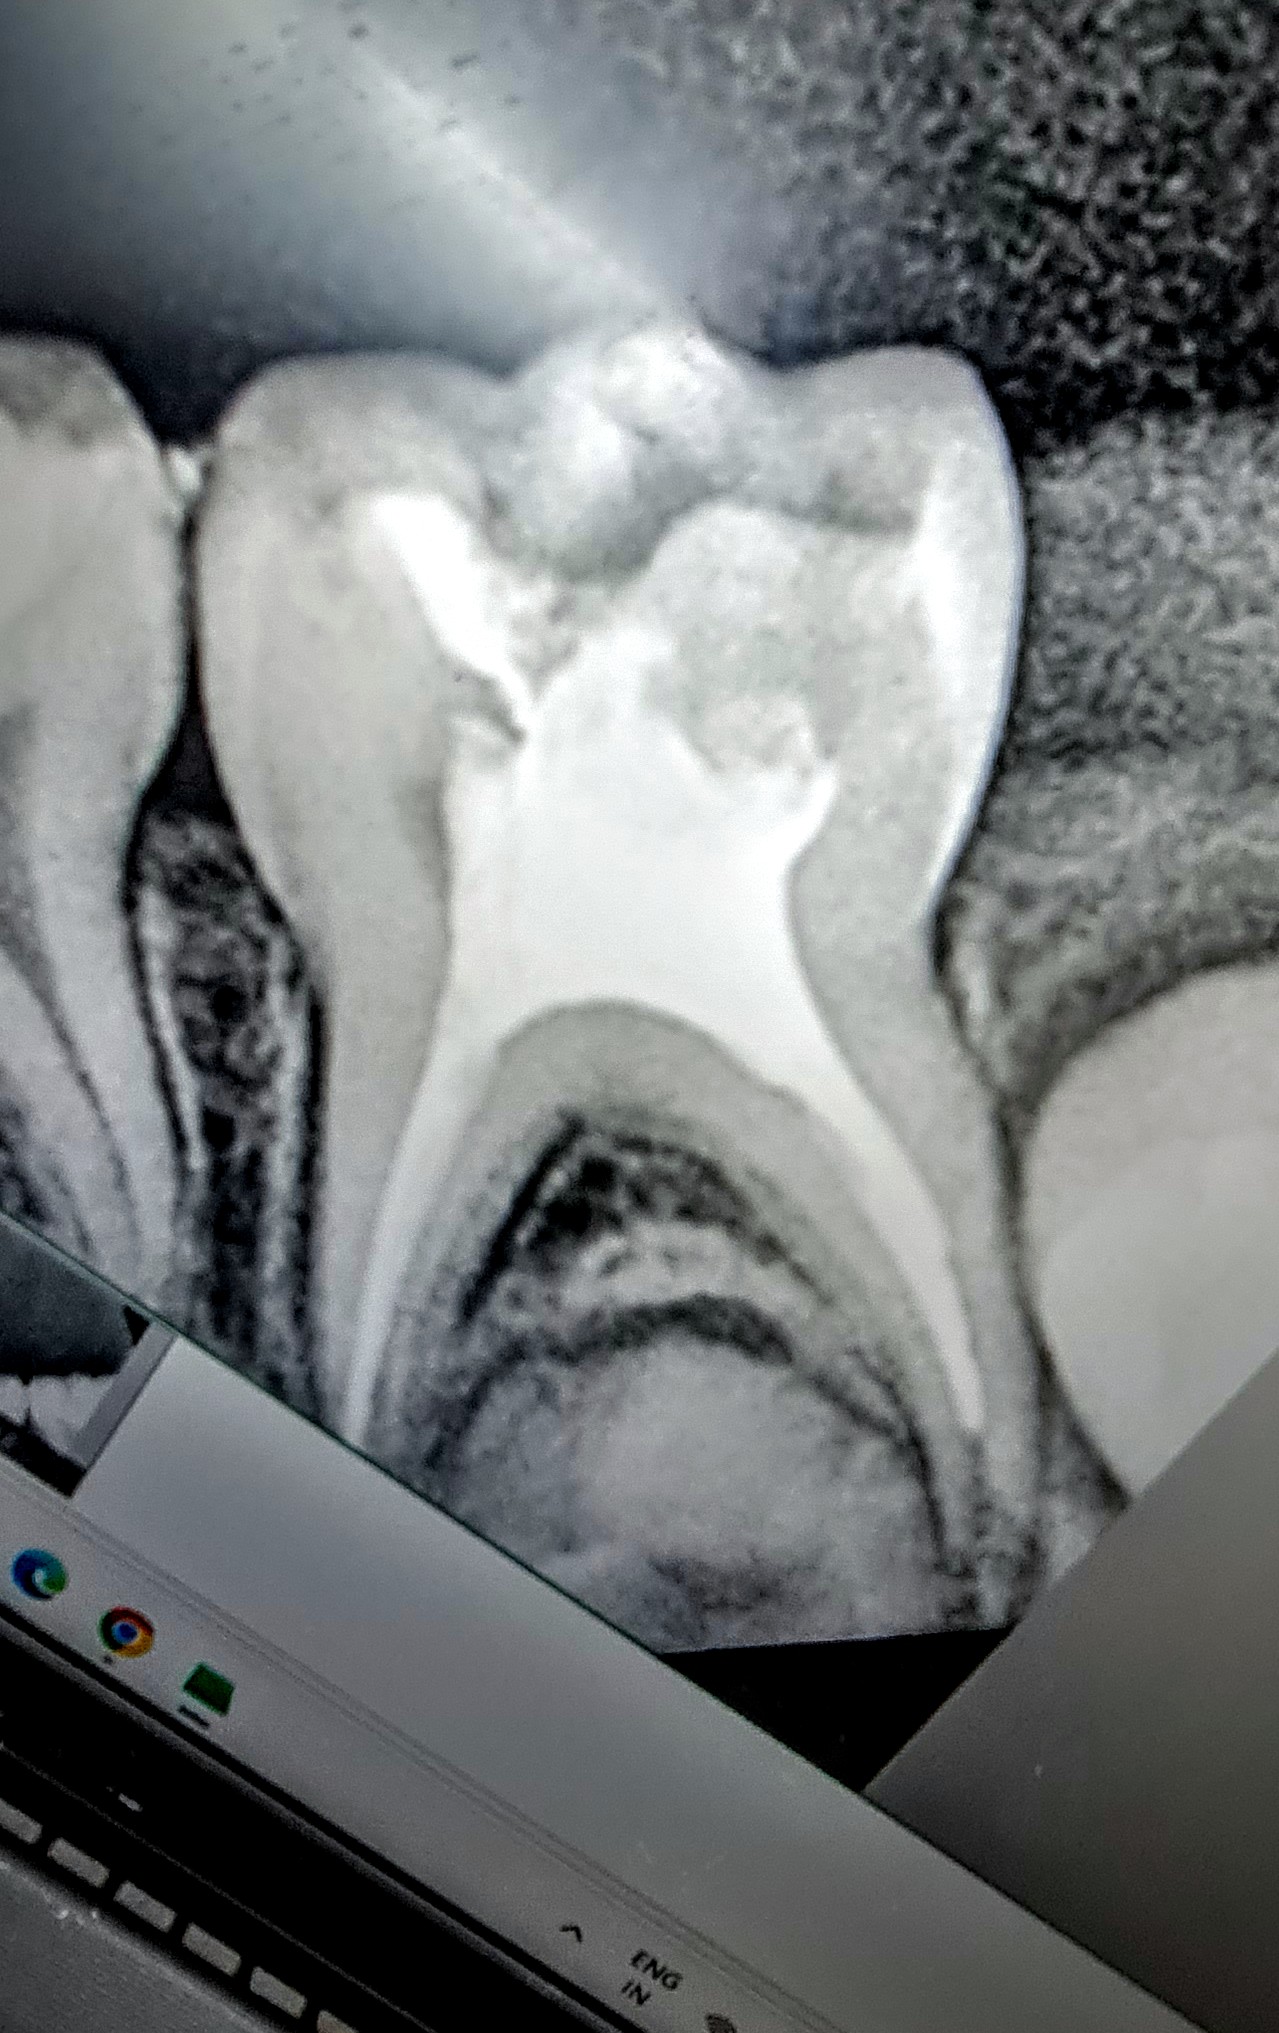

Best Kids Dentist in Rohini ! Get The Best Dental Treatment for your Kids at Smiles For All Dental Clinic , The Best Dental Clinic in Rohini Sector 11. We have Dr.Aman Jain (Kids Dentist) who makes sure that the Treatment your Kids get is a fun filled and a pain free one! Contact us to book your appointment.